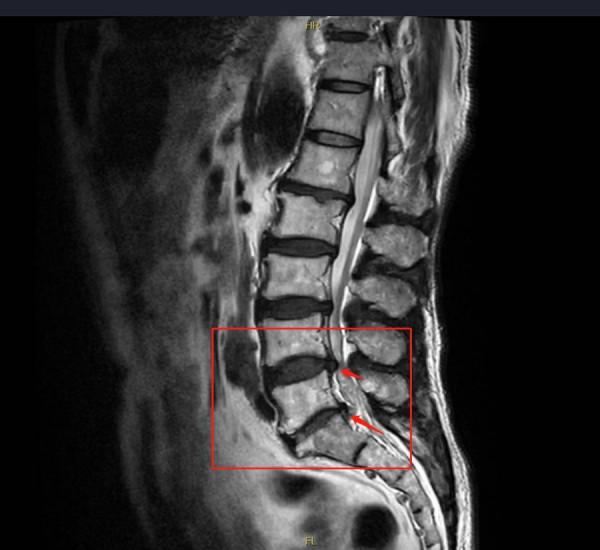

71歲的患者王先生腰痛伴雙臀部麻木15年,曾於當地醫院就診檢查為腰椎間盤突出症,醫生建議口服止痛藥、中藥及腰部針刀治療,症狀未得緩解。半個月前,王先生症狀加重,並感腰部疼痛自雙臀部經雙股外後側放射至雙小腿後側,疼痛發覆發作,嚴重影響其日常生活及睡眠。

近期王先生慕名來到濟南南郊醫院,經骨二科副主任醫師管玉傑仔細詢問病史和相關檢查,診斷為腰椎管狹窄症(L4/5、L5/S1);腰1、2椎體血管瘤。“患者病史長、症狀重、嚴重影響日常生活,為避免神經進一步損傷,維持脊柱穩定性,需儘早進行手術治療。”骨二科醫師團隊進行病案討論後,最終為王先生制定了腰4/5、腰5/骶1椎管減壓+椎間盤切除術+椎間植骨融合釘棒內固定術的微創手術方案。